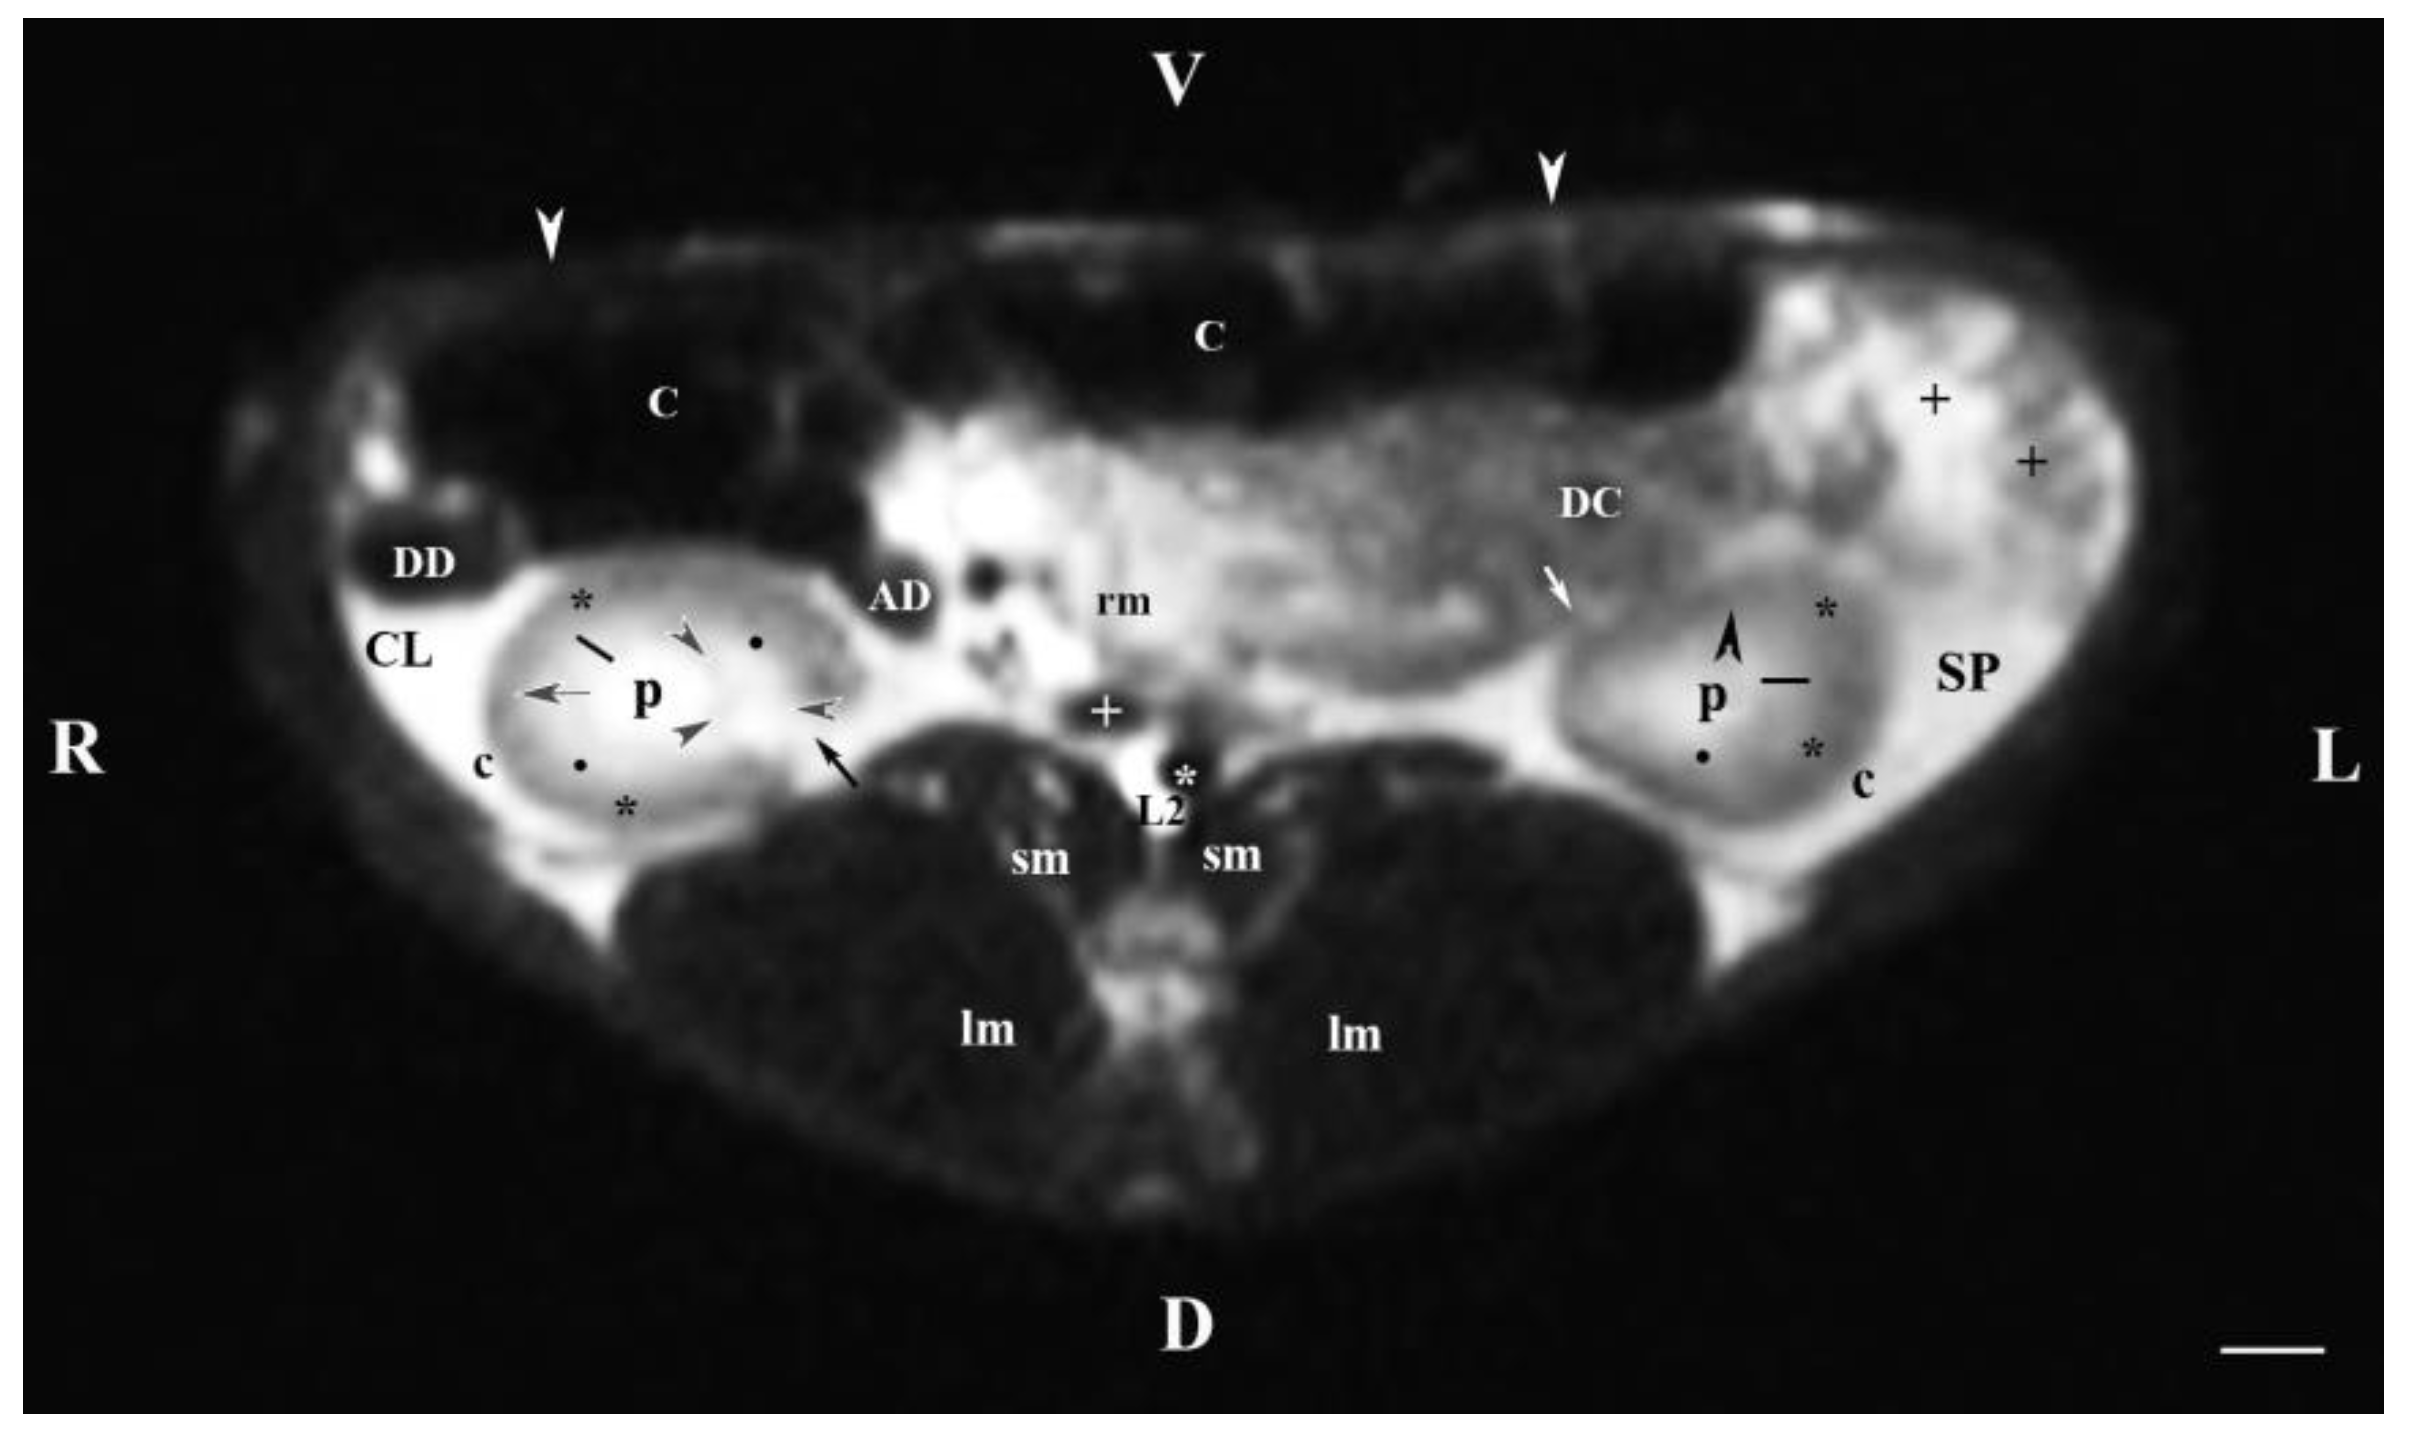

Transverse MRI (Т2-weighted sequence) through L2 showed both kidneys: the cranial part of the left one and the middle part of the right one. The hyper intense hilus of the right kidney with the beginning of the ureter, dorsolateral to the hypo intense signal of the ascending duodenum, were seen dorsomedially (Figure 2). The descending colon was visualized ventrally to the beginning of the left ureter. The dorsal and ventral kidney recesses appeared as hypo intense oval findings between the kidney pelvis and the medulla. The corticomedullary definition at the left kidney was well represented. The left kidney image had an almost triangular transverse profile, surrounded by the hyper intense adipose capsule separating it from the spleenthe latter being lateral to the renal finding. The proximal end of the ureter was seen as hypo intense tubular finding at the ventromedial border of the left kidney. The distance between images of the left kidney and medially located hypo intense image of the abdominal aorta was significantly greater than the distance from the right kidney and medially located hypointense caudal vena cava (Figure 2). The root of the mesentery appeared ventral to the aorta and caudal vena cava and medial to both kidneys as a heterogeneous hyper intense finding with irregular borders. The heterogeneous hyper intense images of the descending colon and jejunum with mesentery and the large hypo intense caecal image were visualized ventral to the left kidney. The difference in signals of the left kidney inner and outer medullary parts was similar to the pattern of the right kidney. The fibrous capsule of the left kidney appeared as a thickened linear hypo intense finding in comparison with the capsule of the contralateral kidney (Figure 2).

The transverse T2-weighted image through L2 showed images from both kidneys, the right one was closer to the median plane (caudal vena cava and abdominal aorta) than the left one. The different definition and informative value of images of the two kidneys confirmed the cranial localization of the right kidney in relation to the left one. The hilus and the beginning of the right ureter appeared at the dorsomedial border of the kidney, whereas at the left kidney they appeared at the ventromedial part—an important sign about bilateral difference in the rabbit renal topography. The hypo intense kidney recesses were visualized in the dorsal and ventral part of kidneys, close to the renal pelvis. The anatomical contact between the right kidney and the caudate liver lobe, as well as that between the left kidney and the spleen were demarcated. The sharp transition of the image signal from low towards high intensity of studied tissues was due to the different amount of interstitial fluids. The adipose capsule image between contacting surfaces of various signal intensity was not found, and only the linear hypo intense fibrous capsule was presented. The shape of the renal pelvis and that of the respective kidney was similar for both kidneys. The kidney shape was distinguished with bilateral difference (oval right and triangular left kidney), which is a species-specific image morphological trait.

Figure 2. MRI imaging anatomy of organs from the middle abdominal region (transverse section at the L2 level); R-right; L-left; D-dorsal; V-ventral; (T2-weighted sequence). (C) caecum; (DC) descending colon; (black cross) jejunum; (SP) spleen; (lm) longissimus muscle; (sm) psoas muscles; (rm) root of mesentery; (white star) abdominal aorta; (white cross) caudal vena cava; (black star) renal cortex; (p) renal pelvis; (black horizontal arrow and black point) right renal corticomedullary junction; (black perpendicular arrowhead) external medullary part; (white oblique arrow) commencement of the left ureter; (CL) caudate lobe; (DD) descending duodenum; (AD) ascending duodenum, (c) adipose capsule; (oblique black arrowhead) dorsal and ventral renal recess; (oblique black arrow) renal hilus and commencement of the right ureter; (white perpendicular arrowhead) abdominal wall. Line=10mm.